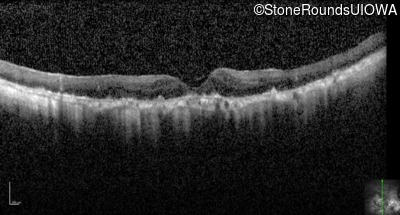

Optical Coherence Tomography - Right - 3/120

Exemplar / OCT Stack

OCT Stack